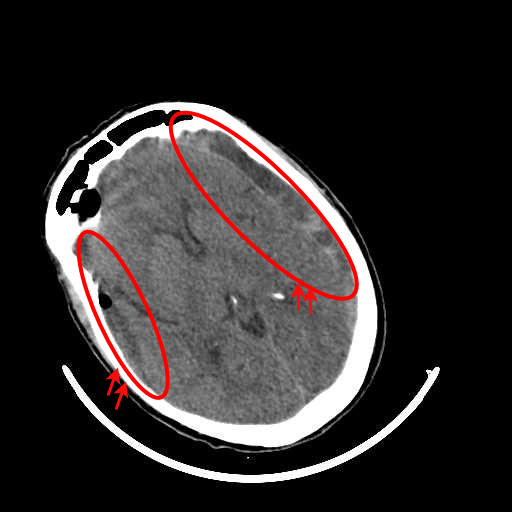

(b) CT scan of a brain with ICH

Figure 2: (a) CT scan of a normal brain without any signs of hemorrhage, (b) CT scan of a brain with ICH, illustrating visible regions of bleeding.